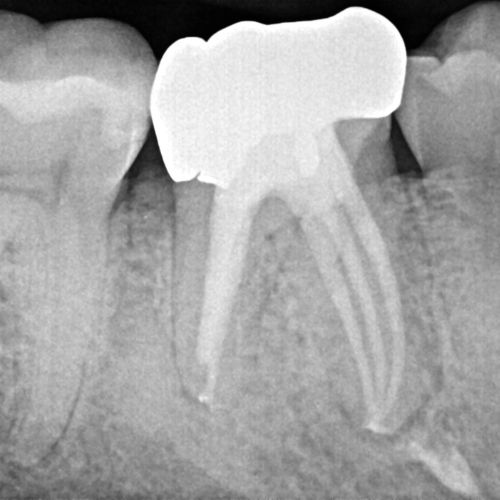

Case 2

This is a retreatment case. The picture on the left shows a lower molar that had been root canal treated many years prior, but either did not heal or at some point afterward became re-infected. The lesion is quite large, extending to the inferior alveolar nerve. While retreating the case Dr Cottle found a previously missed nerve canal (three in one root, five total in this one molar) and was able to disinfect all the canals again. The image on the right shows the completely healed bone one year later.